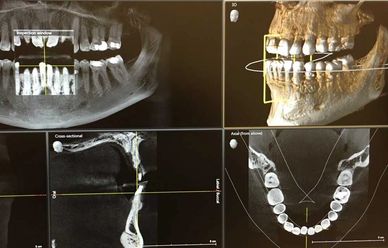

At Memorial Drive we use the latest 3D X-Ray technology to provide our patients with the highest level of dental care. ln July of 2018 a CBCT 3D Conebeam was installed in our practice to be used in the aid of better diagnosis for Pathology, Root Canal treatment, and the placement of Dental lmplants. 3D helps dentists make more accurate diagnoses, resulting in better treatment. Better imagery means we can pinpoint dental problems at their onset, allowing for early intervention, typically resulting in less invasive, less costly dental work. Less Radiation Exposure. With 3D technology, patients aren’t exposed to unnecessary radiation.

Better imaging means better results. Not all dentist offices are created equal. In fact, there can be a wide discrepancy in the quality of treatment patients receive, particularly if a dental office doesn’t invest in the latest technology. At Memorial Drive we use the latest 3D X-Ray technology to provide our patients with the highest level of dental care. Our doctors and staff frequently attend continuing education seminars to learn the latest dental techniques.